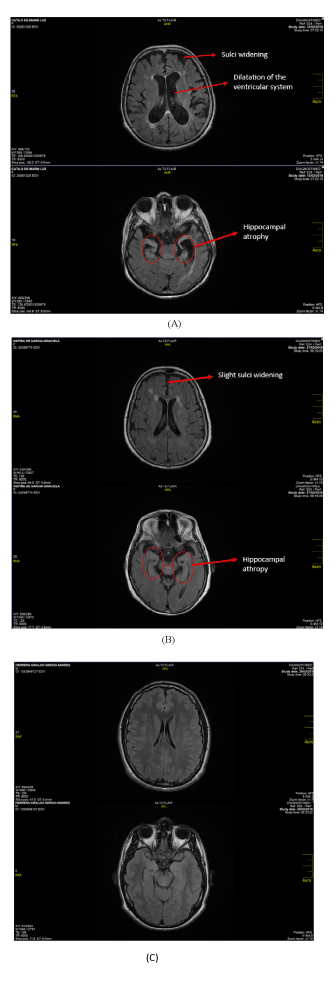

Figures 8. A. shows the comparative MRI results from patients clinically diagnosed with Alzheimer’s versus healthy patients, using extract of yeast DNA β-Amyloid sensor. B. shows the MRI of pre-Alzheimer’s patient (5) using extract of yeast DNA β -Amyloid sensor. C. shows the MRI of a healthy patient without encephalic alterations [24] using extract of yeast DNA β-Amyloid sensor